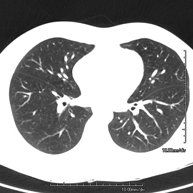

- TC Tórax alta resolución Prueba diagnóstica que consiste en el estudio del pulmón mediante el empleo de un equipo de TC (Tomografía Computarizada) obteniendo imágenes bi y tridimensionales que permiten un estudio anatómico altamente específico del pulmón, pudiendo valorar estructuras anatómicas de tamaño muy pequeño. Es una técnica muy importante en el estudio de los pacientes con sospecha de enfermedad pulmonar. Prueba diagnóstica que consiste en el estudio del pulmón mediante el empleo de un equipo de TC (Tomografía Computarizada) obteniendo imágenes bi y tridimensionales que permiten un estudio anatómico altamente específico del pulmón, pudiendo valorar estructuras anatómicas de tamaño muy pequeño. Es una técnica muy importante en el estudio de los pacientes con sospecha de enfermedad pulmonar.

- TC Tòrax Prova diagnòstica que consisteix en obtenir imatges del tòrax d'alta definició anatòmica (pulmons, cor, mediastí, grans vasos, caixa toràcica, etc.) mitjançant l'ús d'un equip de TC (Tomografia Computeritzada). Aquestes imatges s'estudien posteriorment en una estació de treball que permet reconstruccions bidimensionals en diferents plans de l'espai i també reconstruccions tridimensionals (3D: volumètriques). Alguns estudis requereixen l'ús de contrast iodat per millorar la definició de les imatges. Prova diagnòstica que consisteix en obtenir imatges del tòrax d'alta definició anatòmica (pulmons, cor, mediastí, grans vasos, caixa toràcica, etc.) mitjançant l'ús d'un equip de TC (Tomografia Computeritzada). Aquestes imatges s'estudien posteriorment en una estació de treball que permet reconstruccions bidimensionals en diferents plans de l'espai i també reconstruccions tridimensionals (3D: volumètriques). Alguns estudis requereixen l'ús de contrast iodat per millorar la definició de les imatges.